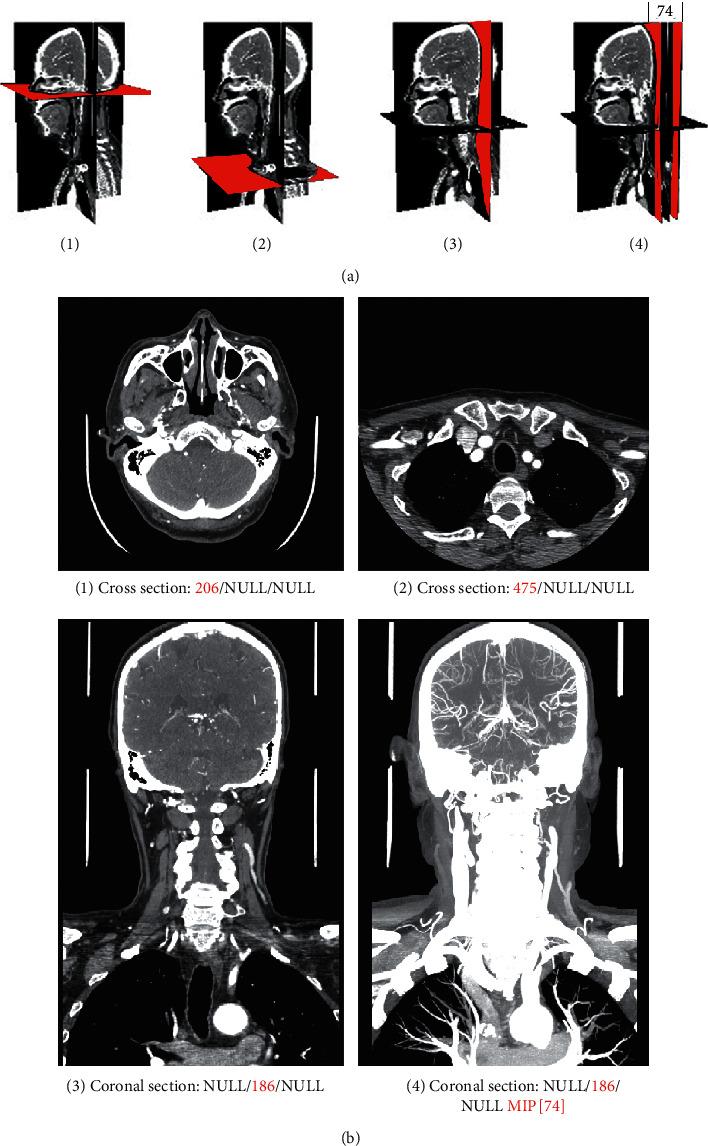

A four-level endpoint network penetration scheme based on the existing hospital network facilities and information security rules was proposed to realize the secure and lightweight sharing of SMIs over the Internet. A "Master-Slave" interaction to the interactive characteristics of multiplanar reconstruction and maximum/minimum/average intensity projection was designed to enhance the user experience. Finally, a prototype system was established.

提出了一种基于现有医院网络设施和信息安全规则的四级端点网络穿透方案,以实现互联网上安全、轻量级的 SMI 共享。根据多平面重建和最大/最小/平均强度投影的交互特点,设计了“主-从”交互,以增强用户体验。最后,建立了一个原型系统。